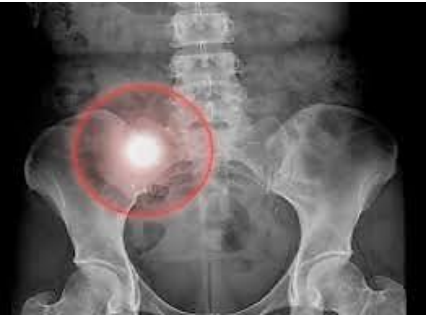

Nas radiografias, essas alterações aparecem como manchas mais brancas que o osso ao seu redor, conforme na imagem abaixo.

O achado é sugestivo de